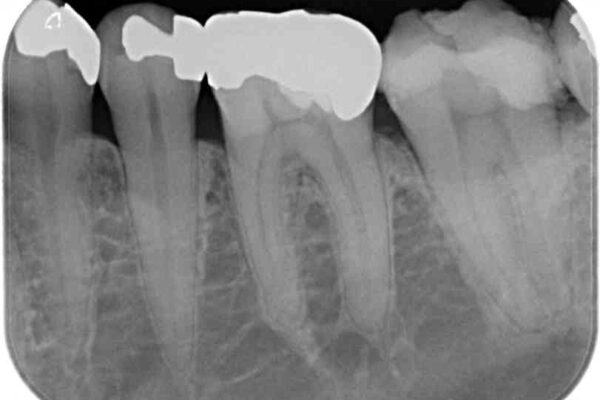

診査をしたところ、神経組織に影響を及ぼすような大きな虫歯があることが分かりました。

虫歯が歯髄腔(神経の部屋)に達している可能性が非常に高かったため、炎症を起こしている神経組織を部分的に切除し、歯根部分の神経組織を保存する治療法が望ましいと考えられました。

虫歯は深くまで進行しており、歯冠部の神経から出血が認められました。神経を部分的に除去したところ出血が治まったので、生体親和性の非常に高いセメントにて充填し、仮封をしました。

後日状態を確認したところ、残された神経に異常は認められませんでした。

• 治療をしても違和感の続く奥歯 神経を極力残した虫歯治療 治療前画像